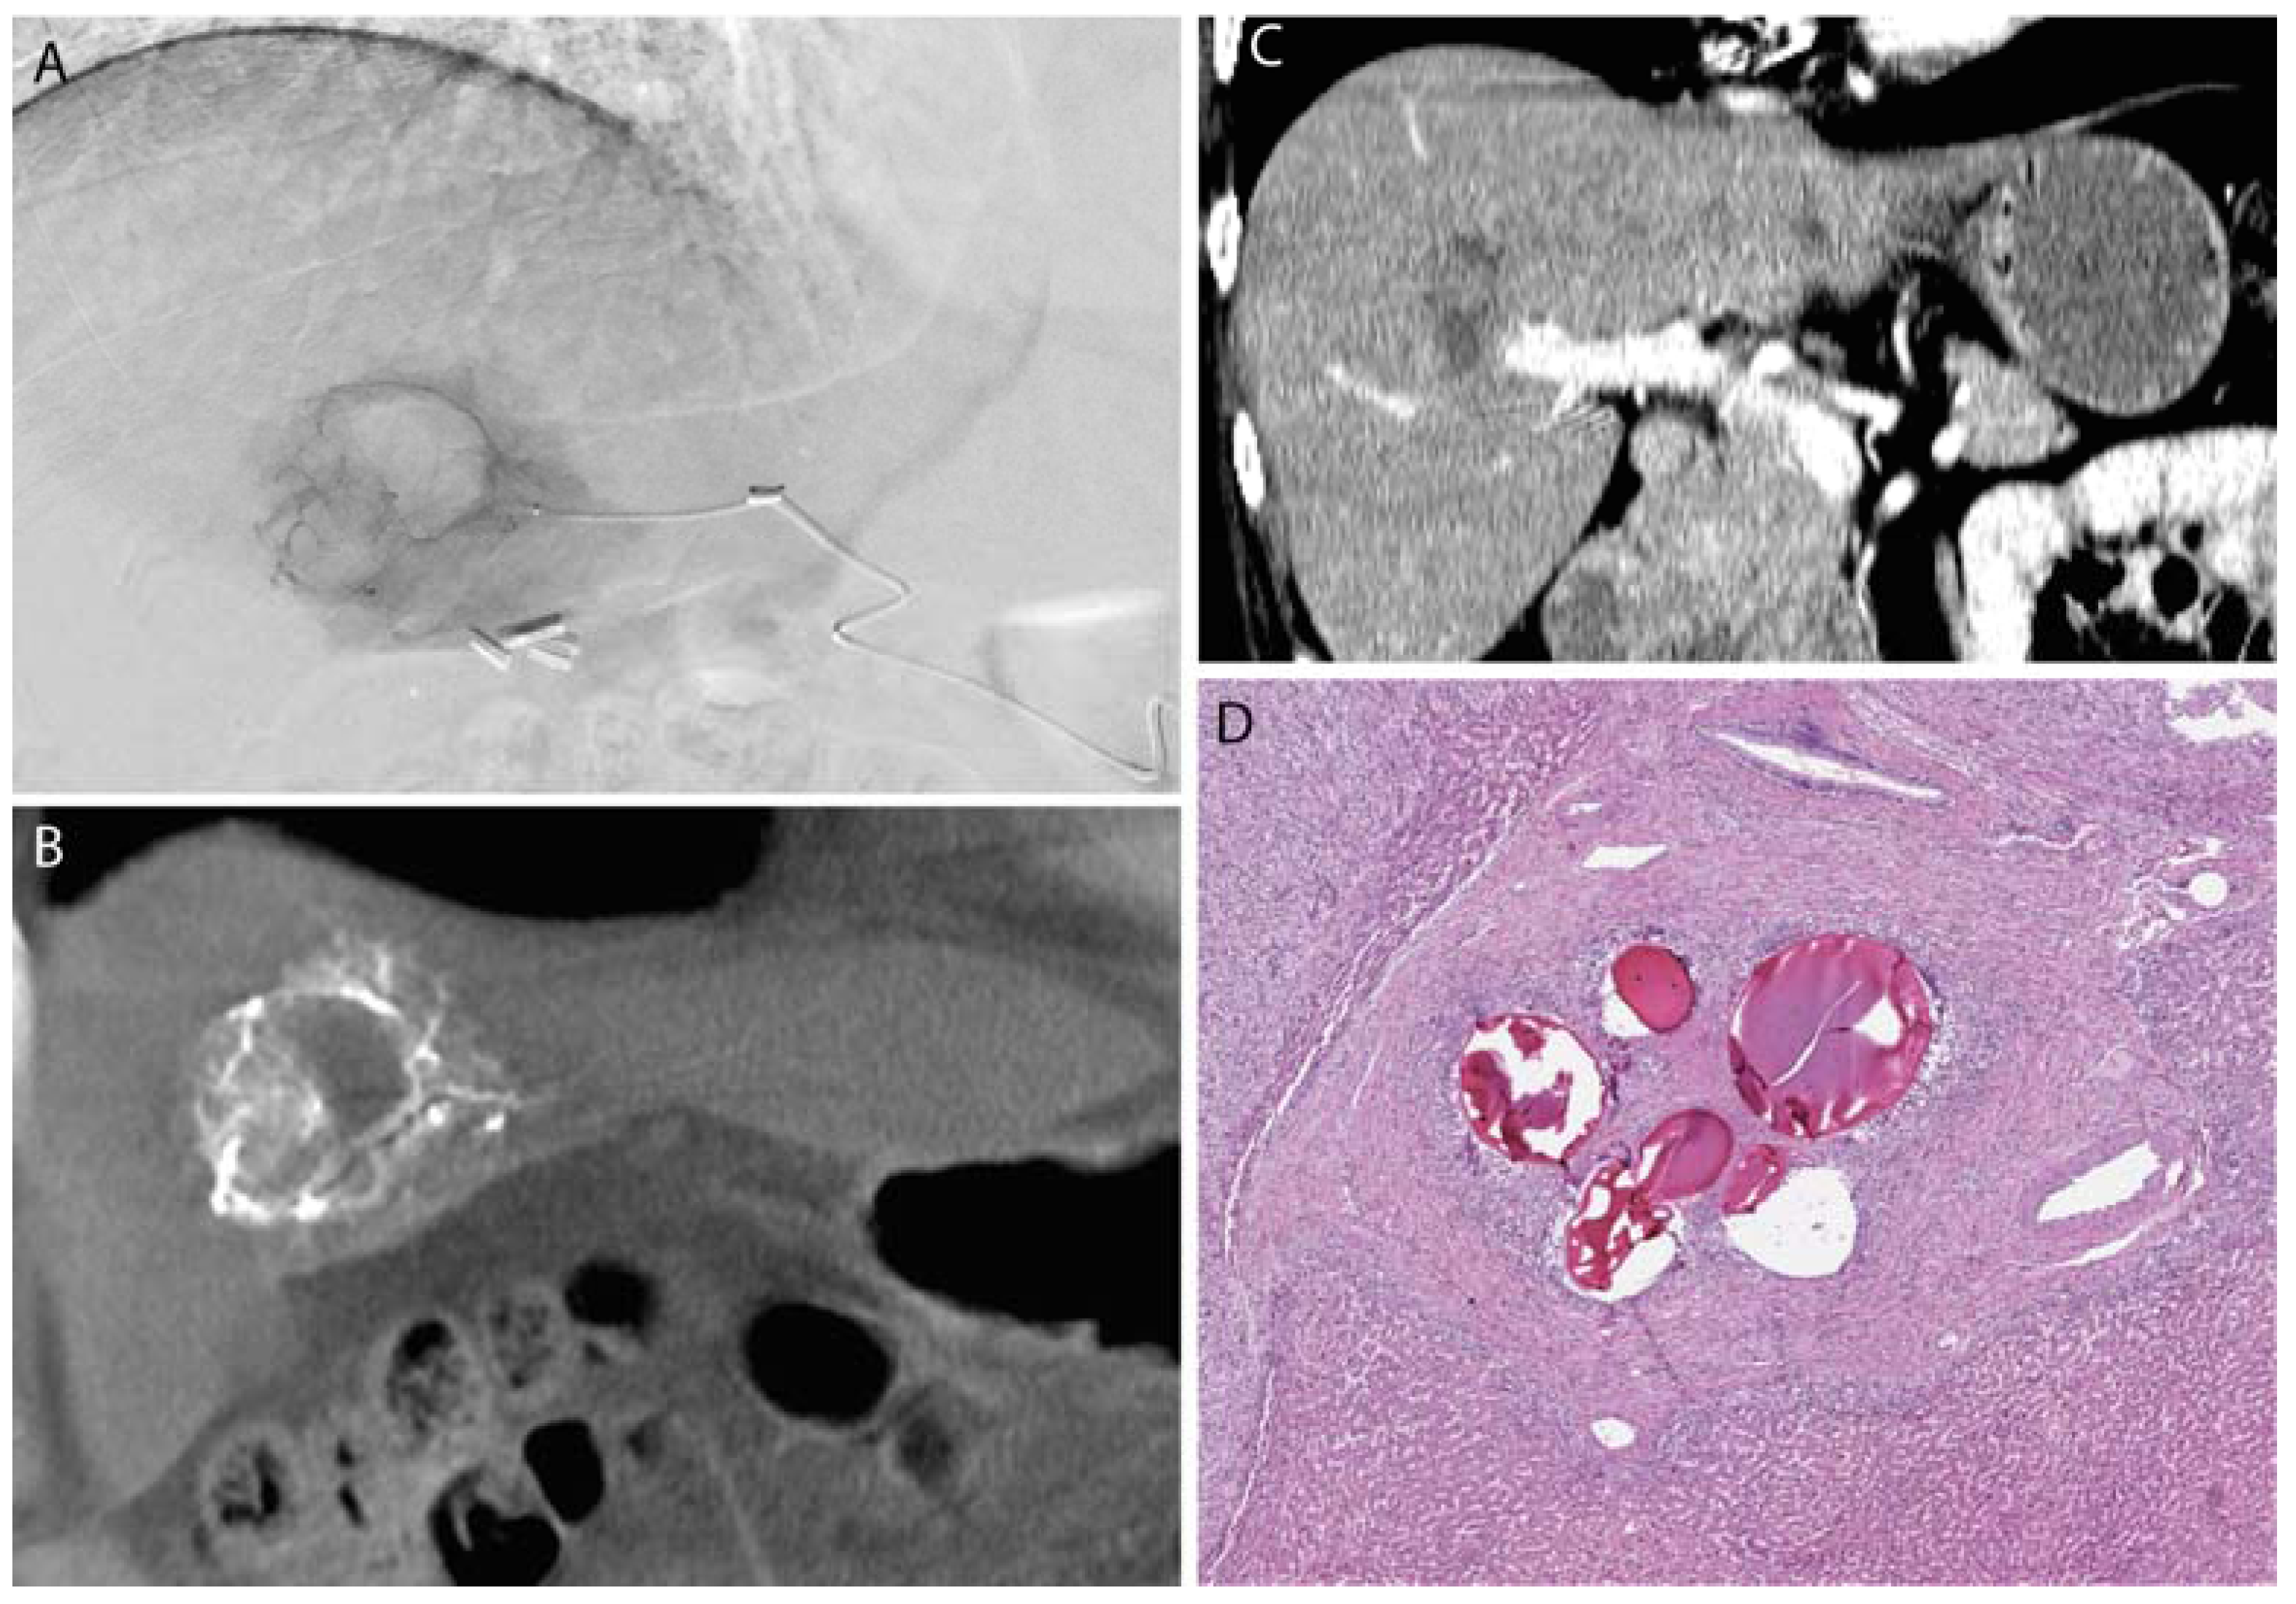

3.1. Polyvinyl Alcohol Particles

3.2. Gelatin Sponge

3.3. Microspheres